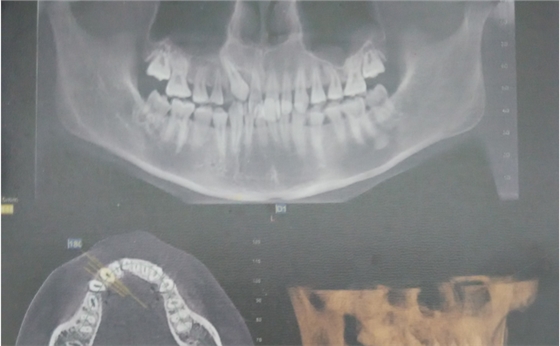

圖6.術(shù)前CBCT影像檢查:13位于腭側(cè)。準(zhǔn)確定位,為下一步切除牙齦組織打好基礎(chǔ)。